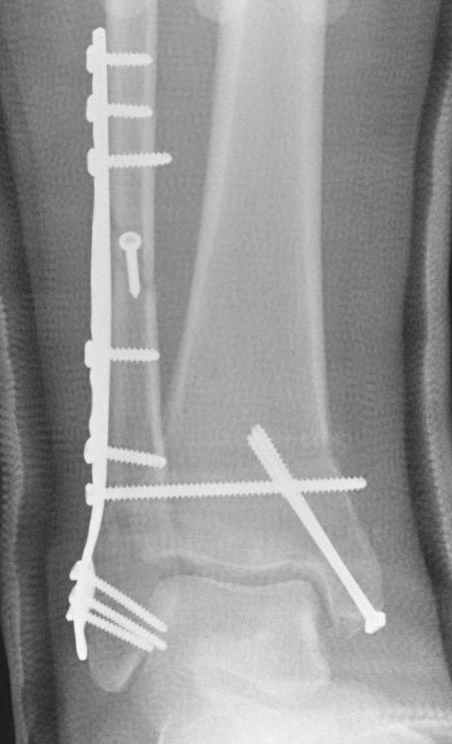

15 ноября прямой

|

15 ноября боковой

15 ноября трехчетвертной